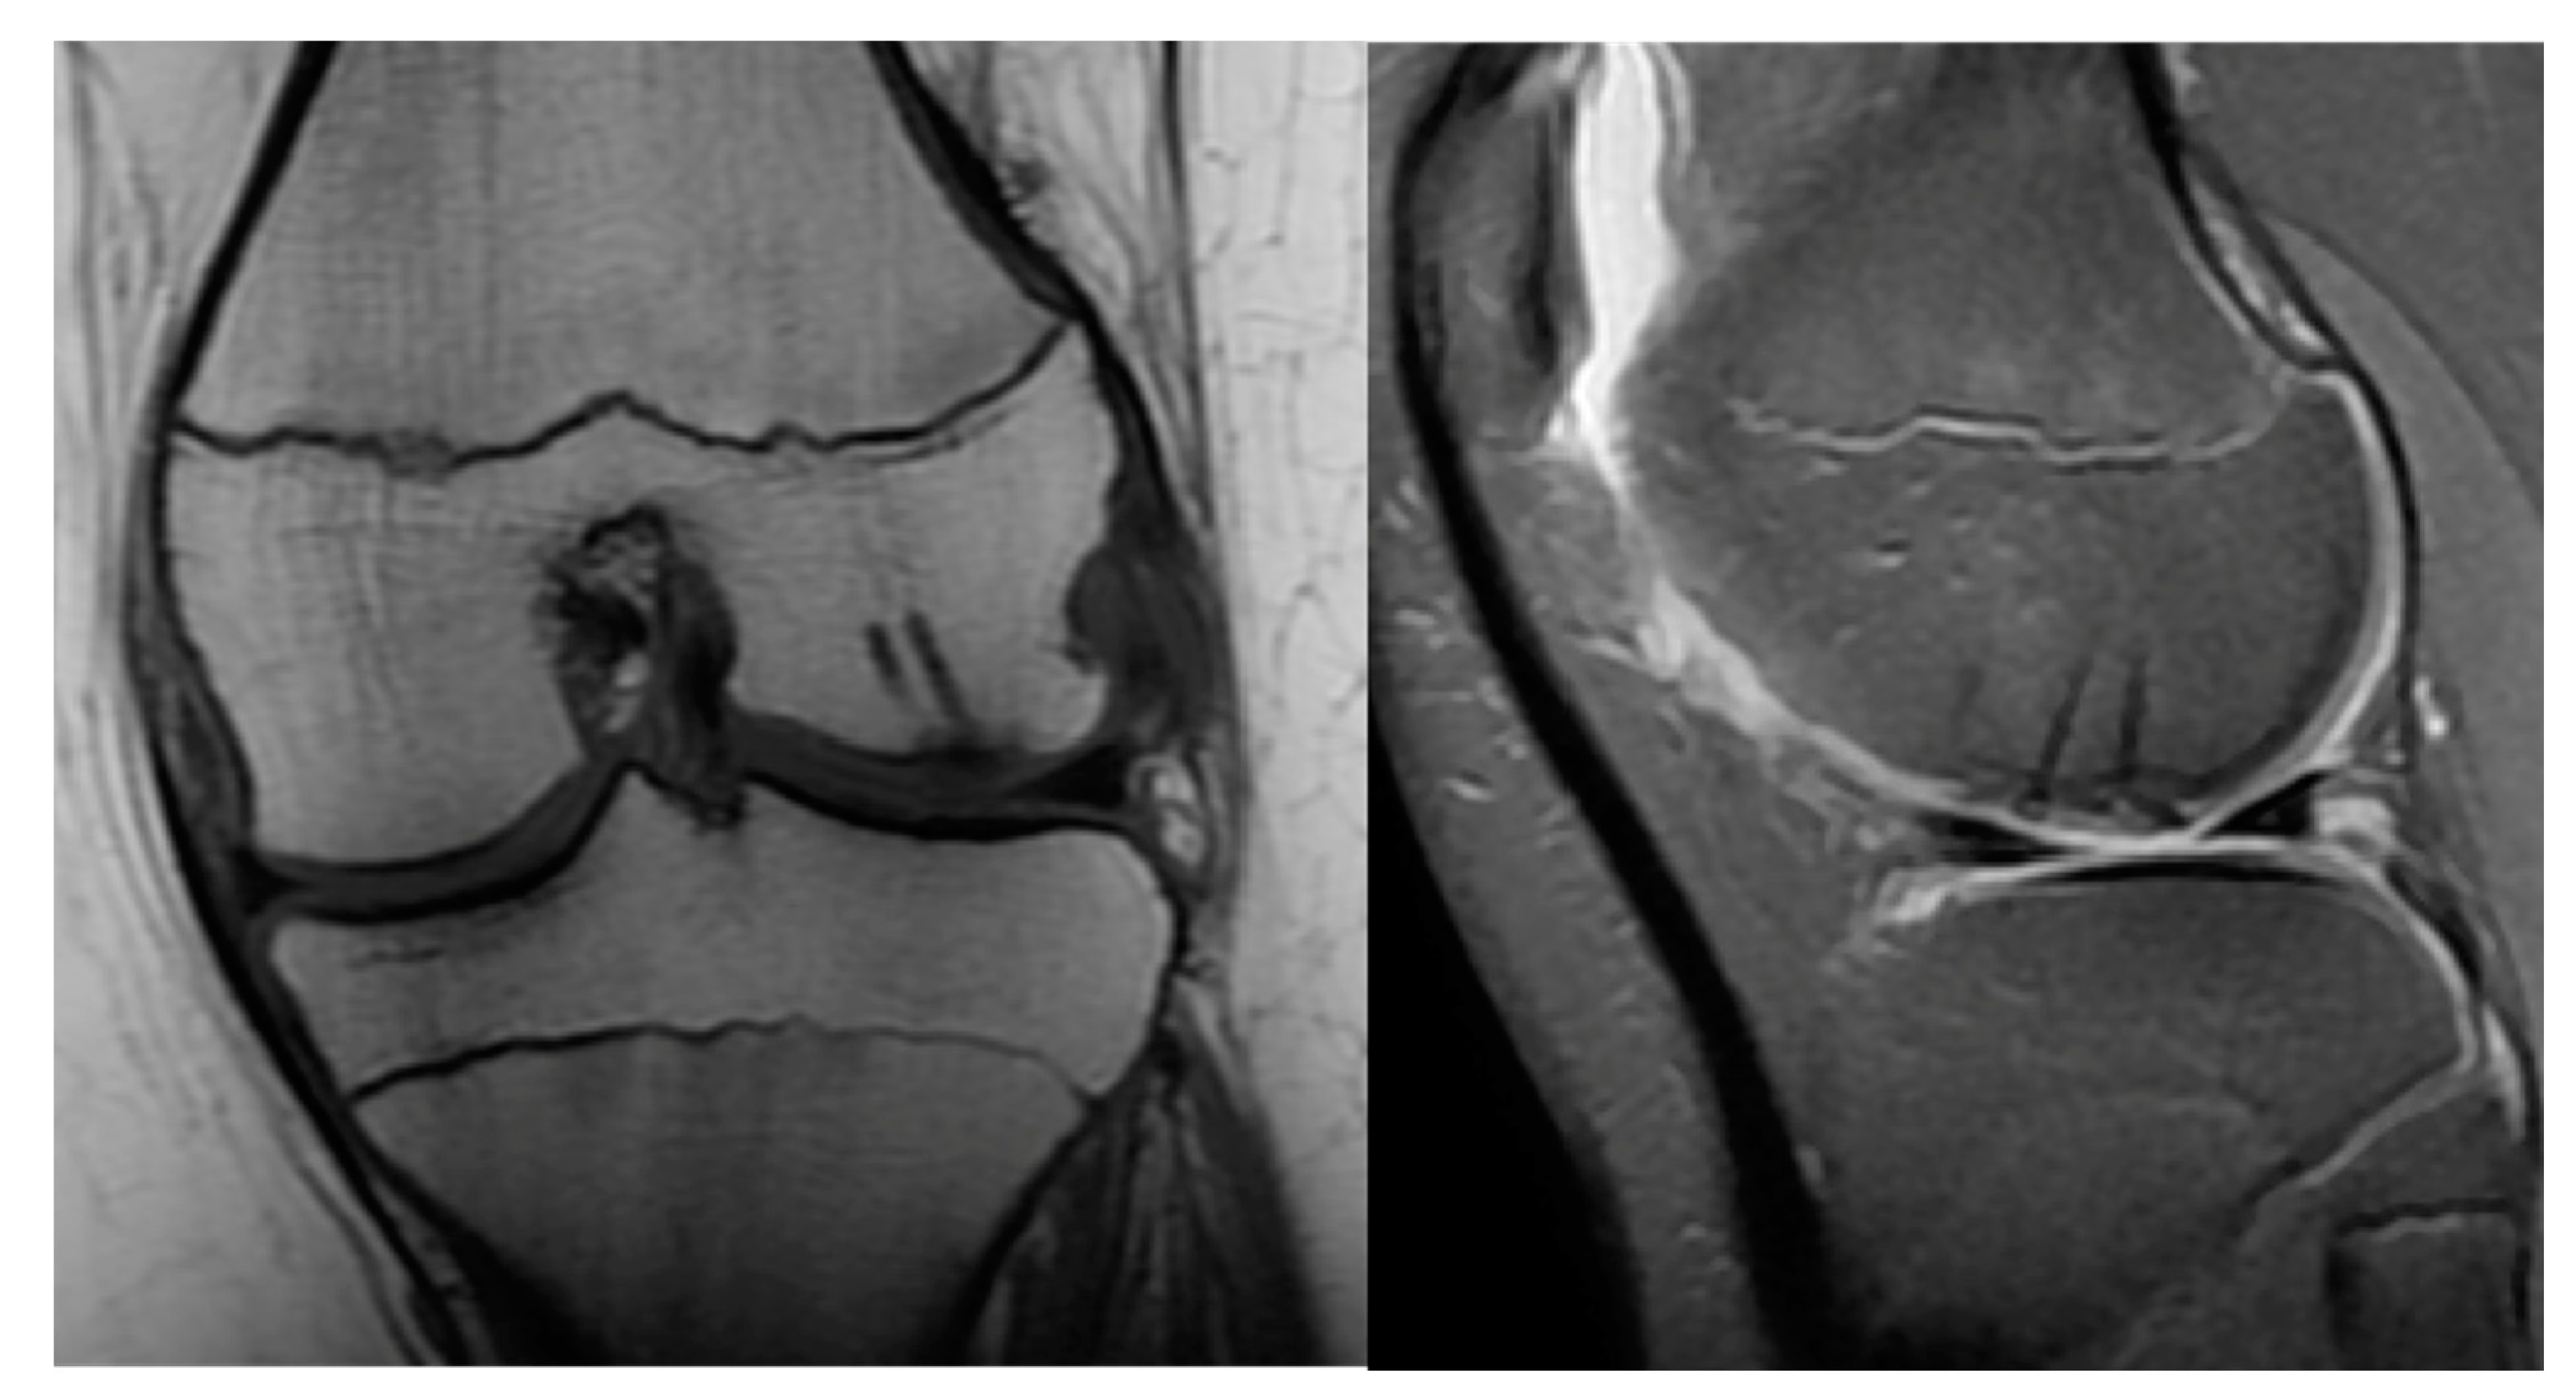

- MRI: Rim-sign - high signal around fragment

- Type A: Cystic on CT and Edema on MRI

- Type B: Non-displaced and incompletely undercut by fluid (MRI) and lucency (CT) with an open connection to the articular cartilage.